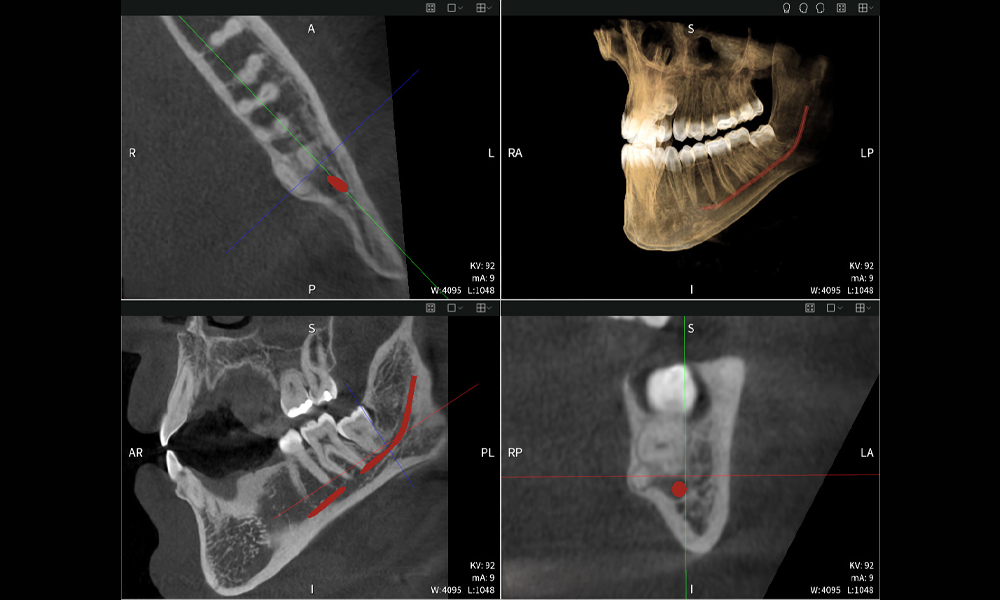

Nachstehend finden Sie einen Fall von Dr. med. dent. Oliver A. Centrella, in dem die CBCT-Aufnahmen mit Seethrough Max entscheidende Informationen zur komplexen Anatomie sowie zur kritischen Beziehung zwischen den Weisheitszähnen und dem Nervus alveolaris inferior lieferten. Bei diesem Fall besteht eine Indikation zur chirurgischen Entfernung der Weisheitszähne.

Abbildung a

- Oben links: Axiale Schnittansicht des linken Unterkiefers (Region 38) mit Darstellung des Nervus alveolaris inferior (rot) in unmittelbarer Nähe zu den Wurzeln des Zahns 38.

- Oben rechts: 3D-Rekonstruktion des gesamten Unterkiefers zur Orientierung. Der rot markierte Nervus alveolaris inferior verdeutlicht seine Lage im Kieferknochen.

- Unten links: Sagittale Ansicht des Unterkiefers (Region 38), die die enge räumliche Beziehung zwischen den Wurzeln und dem Nervenkanal verdeutlicht.

- Unten rechts: Koronale Ansicht des Unterkiefers (Region 38) entscheidend für die Beurteilung der räumlichen Lage der Wurzeln zum Nerven.